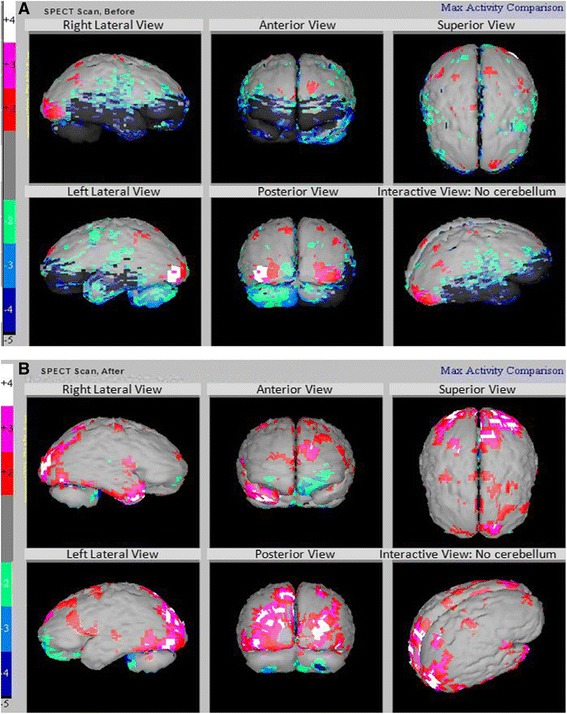

我們能夠在治療前后對所有患者進行SPECT掃描?;颊叩腟PECT掃描顯示在接受hESC治療后灌注得到改善。我們一位患者的SPECT掃描報告如圖3A和B。

圖3:腦癱患者的 SPECT 掃描

圖3:腦癱患者的 SPECT 掃描(灰色 – 正常;紅色、粉紅色和白色 – 高于正常水平;綠色、淺/深藍色、黑色 – 低灌注)。

A)

在接受hESC治療之前顯示灌注不足的區域。

B)接受hESC治療后灌注改善(黑色區域減少)。